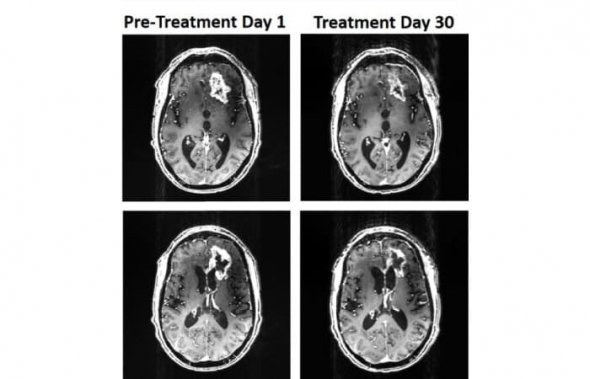

У травні 2018 року 53-річний пацієнт звернувся до лікаря через зміну психічного стану. Медики й виявили пухлину, яка росла попри лікування та операцію. Оскільки традиційні методи лікування вже не допомагали, лікарі запропонували пацієнту випробувати магнітний шолом. Процес лікування тривав 36 днів. За цей час гліобластома зменшилася на 31%, а у хворого покращилася мова й когнітивні функції.